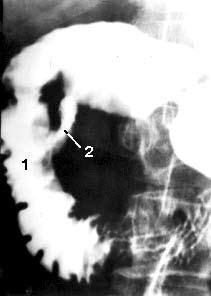

Рентгенологические исследования. Рентгенологическое контрастное исследование ДПК позволяет выявить патологический процесс, располагающийся не только в самой кишке, но и в органах, непосредственно прилежащих к ней. Применение релаксационной дуоденографии позволяет, как правило, обнаружить опухоль большого дуоденального сосочка и в некоторых случаях, по косвенным признакам, головки ПЖ, а также судить о состоянии стенок самой ДПК. Деформация контуров, сужение просвета ДПК, развернутость ее петли являются косвенными признаками, позволяющими высказать предположение о наличии патологических изменений в ПЖ только в том случае, если опухоль достигнет значительной величины. При РПЖ отклонения от нормы выявляют лишь у 50 % больных (рис. 105).

Рис. 105. Дуоденография в условиях гипотонии больной С. По медиальному контуру двенадцатиперстной кишки в верхней половине нисходящей части кишки имеется участок отсутствия рельефа слизистой оболочки на протяжении 2 см (1) и затекание контраста за пределы кишки – полость распавшейся опухоли (2). Макропрепарат после операции (см. рис. 106)